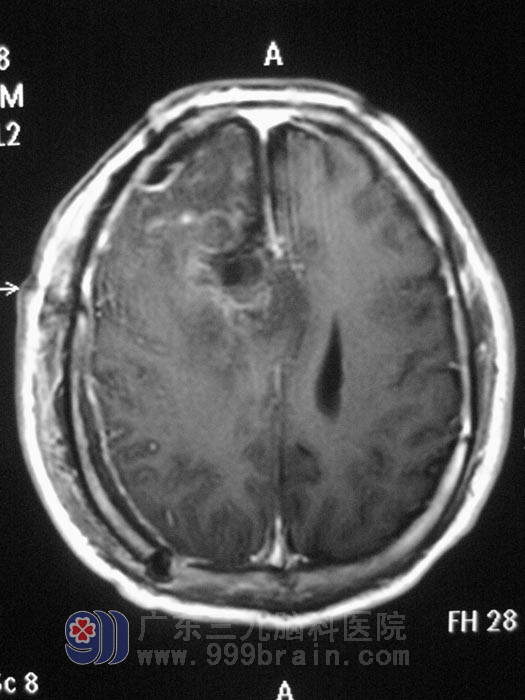

术后第三天查体:神志清醒,问答切题,瞳孔等大等圆,对光发射灵敏,双侧颜面部痛温觉对称,嘴角无偏斜,鼻唇沟对称,伸舌居中,吞咽反射存在,颈软,四肢运动自如,各项神经系统检查正常。

手术后影像